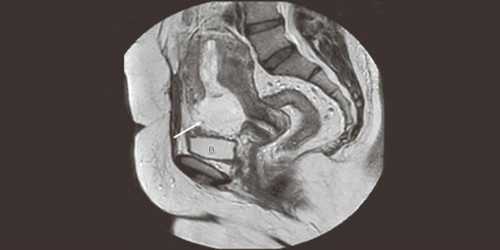

وبعد عمل الفحوصات الطبية تبين أنها حامل في مكان جرح العملية القيصرية السابقة، ويعتبر مكانا صعبا.

وقام الفريق الطبي بإعطاء المريضة عقار "الميزوتركسات" ليوقف نمو الجنين وبعدها تم عمل منظار رحمي لإزالة كيس الرحم ومحتوياته وتنظيف الرحم.